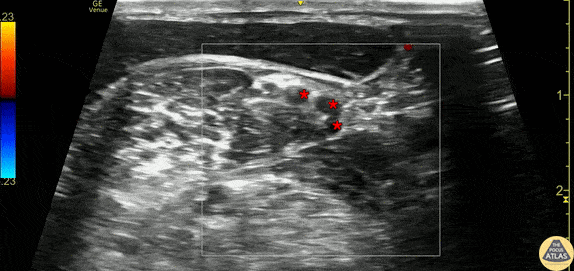

30s M presented with shoulder dislocation. To facilitate reduction, an interscalene nerve block was performed. This clip demonstrates the brachial plexus nerve roots (*) as seen just outside of the interscalene groove - the middle scalene muscle is seen just deep to the nerve roots, with the sternocleidomastoid muscle seen superficial to these. The patient had onset of anesthesia after the block and was able to have closed reduction performed in the ED. Dr. Olivia Serigano, PGY3 Denver Health Residency in Emergency Medicine